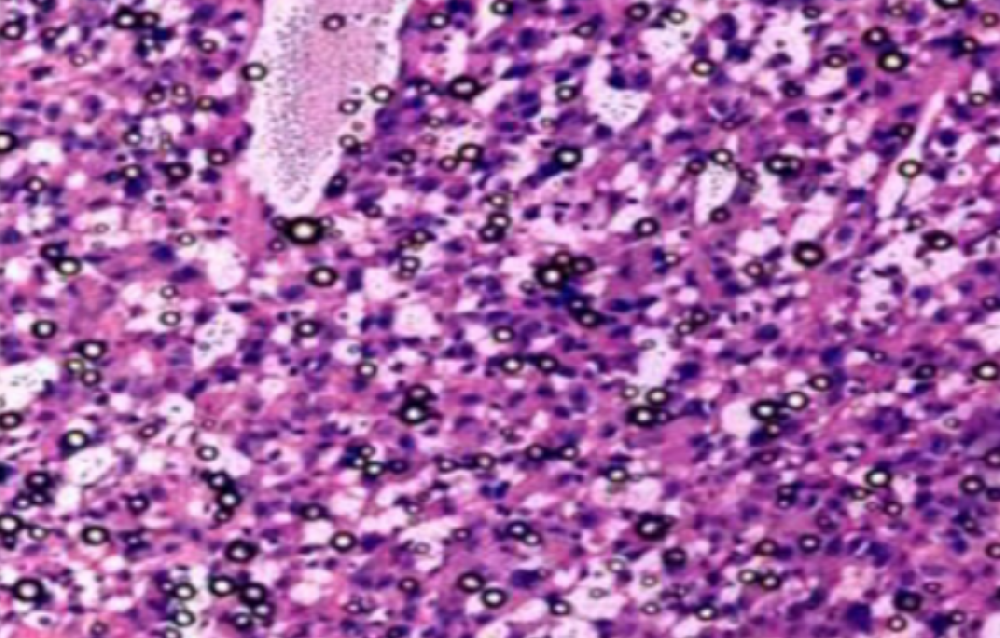

HE染色,全称苏木精-伊红染色法(Hematoxylin and Eosin staining),是最常见的组织切片染色技术之一,用于在显微镜下观察和分析组织或细胞的结构和形态。虽然HE染色是最常见且最基础的染色技术之一,😭但在实验过···

HE染色,全称苏木精-伊红染色法(Hematoxylin and Eosin staining),是最常见的组织切片染色技术之一,用于在显微镜下观察和分析组织或细胞的结构和形态。

虽然HE染色是最常见且最基础的染色技术之一,😭但在实验过程中,很容易出现各种情况导致染色切片质量参差不齐。所以,小编根据以往实验经验,给大家整理归纳出了15个HE染色中的常见问题,还包含问题原因分析以及解决方法哦~

形成原因:切片经梯度乙醇处理后没有完全脱水,导致二甲苯透明、中性树胶封固后残留大量水分。 解决方法:首先移去盖玻片,用二甲苯溶解封固剂如中性树胶,再将切片置入无水乙醇内,待切片重新脱水完全后,用二甲苯透明处理,中性树胶封固。要注意所有用于脱水和透明的液体,在使用一定时间后,应及时更换。 二、细胞核呈红、棕色 形成原因:苏木精染色液过度氧化,切片在苏木精染液染色后返蓝不足。 解决方法:每次染色之前检查苏木精染色液的染色能力,发现苏木精染色液氧化过度应及时更换。此外,切片经苏木精染色后,要给切片以足够的蓝化时间,蓝化过程可用流水、温水、弱碱性溶液(如稀氨水或0.2%碳酸氢钠)等处理。 三、切片在脱蜡后出现大片白色斑点 形成原因:由于烤(烘)片温度太低,切片上的组织蜡膜在脱蜡前没有充分烤(烘)融化。或是因为切片在二甲苯液中停留时间不足,或二甲苯使用过久,造成的脱蜡不彻底。 解决方法:若是由于切片烤(烘)温度低所致,可以先用二甲苯去除切片上的封固胶,然后重新用二甲苯脱去切片上的石蜡,再进行后续染色。若是由于切片在脱蜡的二甲苯中停留时间不足或脱蜡二甲苯使用过久浓度不足所致,则需将切片退回到二甲苯中,停留较长时间,或更换二甲苯液体重新脱蜡,再入乙醇重新脱二甲苯,入0.5%盐酸水溶液褪色后,重新HE染色。 四、细胞核苍白暗淡,即苏木精染色太淡 形成原因:切片在苏木精染色液停留时间太短;苏木精染色液过度氧化,失去染色能力,不能再继续使用;分化步骤处理时间过长;固定不及时。此外值得注意的是,若骨组织细胞核暗淡,大多是脱钙过度造成的。 解决方法:切片重新染色。如果组织在酸性固定液(如Zenker、Bouin)或非中性缓冲甲醛液固定时间过长,细胞核染色能力将减弱,需增加其在苏木精染色液的时间,或用一些方法增加组织的嗜碱性,以改善细胞核的着色。例如,上述组织玻片可以使用Weigert铁苏木精染色液。如果组织是用Zenker液固定的,可将切片脱蜡后放在5%碳酸氢钠溶液3~4h,流水冲洗5min后染色。如果组织是用Bouin液固定的,可将切片脱蜡后放在5%碳酸锂1h,流水冲洗10min后染色。 五、细胞核过染,苏木精染液占据了细胞质 形成原因:玻片在苏木精染色液停留时间过长,或是切片太厚、分化步骤时间太短。 解决方法:如果不是因为切片太厚(用显微镜仔细上下微调,只有一二层细胞核层次),就需将切片进行脱色、漂白、重新染色,适当调整染色和分化时间。但如果确定是由于切片太厚导致的细胞核过染,则需要重新切片。 六、伊红着色淡 形成原因:可能是伊红染液pH值大于5,也可能是蓝化液残留过多,切片太薄,或是切片经伊红染色后在乙醇脱水时间过长。 解决方法:检查伊红染液pH值,必要的话,用乙酸将其调节在4.6~5.0之间,从而使伊红染色色彩艳丽。此外,确保每次蓝化步骤完成后,使用的弱碱性溶液被充分洗去,玻片上没有残留的弱碱性溶液。最后,检查切片的厚度,且脱水时不要让切片在低浓度乙醇中停留时间过长,因为含水多的低浓度乙醇会将切片伊红的颜色分化掉。 七、细胞质过染、分色不足 形成原因:伊红染色液浓度太高,特别是存在焰红燃料、四溴四氯荧光素钠。切片在伊红染色时间过长,或是切片在伊红染色后经乙醇脱水步骤时时间太短,而使乙醇分化伊红的作用不能产生,都能够使细胞质过染。 解决方法:适当稀释伊红染色液,减少伊红染色时间,或使切片在乙醇脱水等步骤时,停留时间相对均匀。同样,也要检查切片的厚度是否合适。 八、切片中出现蓝黑色沉淀物 形成原因:苏木精染色液中的金属膜黏附在玻片上。 解决方法:染色前仔细过滤苏木精染色液,建议使用半氧化苏木精染色液,如Gill苏木精染色液,可以避免过多的金属膜产生。 九、光镜下切片某些区域难以聚焦 形成原因:盖玻片上可能有封固切片的封固剂。 解决方法:移去盖玻片,重新用干净的盖玻片封片。检查切片封片方法,是人工手工封法,还是机器自动封法,如有问题及时调整。 十、封固剂从盖玻片与载玻片之间的缝隙回缩 形成原因:盖玻片弯曲或不平整,或是封固剂含二甲苯过多,稀释过度。 解决方法:移去盖玻片,重新找一张盖玻片,用干净的封固剂封片。如用手工封片法,保证在封固结束时,封固剂容器盖子为紧闭状态。且尽量使用小的容器盛装封固剂,一旦封固剂太黏稠,就可以选择废弃。 十一、细胞核呈灰蓝状态 形成原因:可能由于组织处理温度过高、过热,在液体石蜡中停留的时间过长。或是固定时间太短后,直接在高浓度的乙醇中进行了脱水处理。 解决方法:理论上来说,仅在组织浸蜡步骤才进行加热,组织不能在热蜡液中停留太久。如果由于某些原因不能进行下一步包埋处理,可将组织连同塑料包埋盒一并放置在室温空气中,冷却凝固,以备包埋。待需要包埋时再重新加温直至石蜡融化即可。组织在处理前必须确保固定良好,脱水最好能从低浓度的乙醇开始。 十二、类色素的点状结晶和黑色光滑细胞核 形成原因:这种裸核改变是因为切片封片前放置在空气中的时间太长,以至于二甲苯挥发,切片干燥。 解决方法:移去组织切片上的盖玻片和封固剂,重新处理。将切片水洗数分钟,然后重新脱水、透明、封固。封片过程中要保持组织切片的轻度湿润,尽量不要让其干燥。 十三、染色过淡或过浓 解决方法:如果染色过淡,可以增加染色剂的浓度、延长染色时间或更换新鲜的染色剂;如果染色过浓,则应减少染色剂的浓度或缩短染色时间。 十四、切片出现叠加褶皱 形成原因:新购买的玻片洁净度不够、用镊子撑开切片时操作不够熟练未能平整伸展,或玻片表面有油脂,切片粘贴不牢。另外,烤片时间不足、烤片温度过低或切片过厚造成切片脱落,都会造成重叠或有皱褶的情况。 解决方法:新购买的玻片最好能用硫酸清洁液浸泡一晚,然后流水冲洗干净。在适宜的温度下烤片时间宁长勿短,保证有充足的烤片时间和温度。另外,切片刀要锋利,才能切出厚薄适宜的切片,保证切片不会因为过厚而脱落。 十五、组织残缺不全或有刮划痕迹 形成原因:组织残缺不全是由于切片时修整蜡块时深度不够、组织没有全部暴露于切面。切片的刮划痕迹是由于切片刀的刀锋有缺口、包埋的组织有异物,或是钙化组织、骨组织及包埋石蜡有沙粒造成的。 解决方法:修整蜡块时保证组织块全部暴露于切面,切片时保证切片刀的锋利没刀口。同时在组织取材时去除手术异物和钙化组织。最后,骨组织要完全脱钙,这样可以保证切片的完整和平整美观。 *注:由于实验中导致结果出现误差的原因多种多样,以上内容仅供参考,具体根据实际情况进行判断。